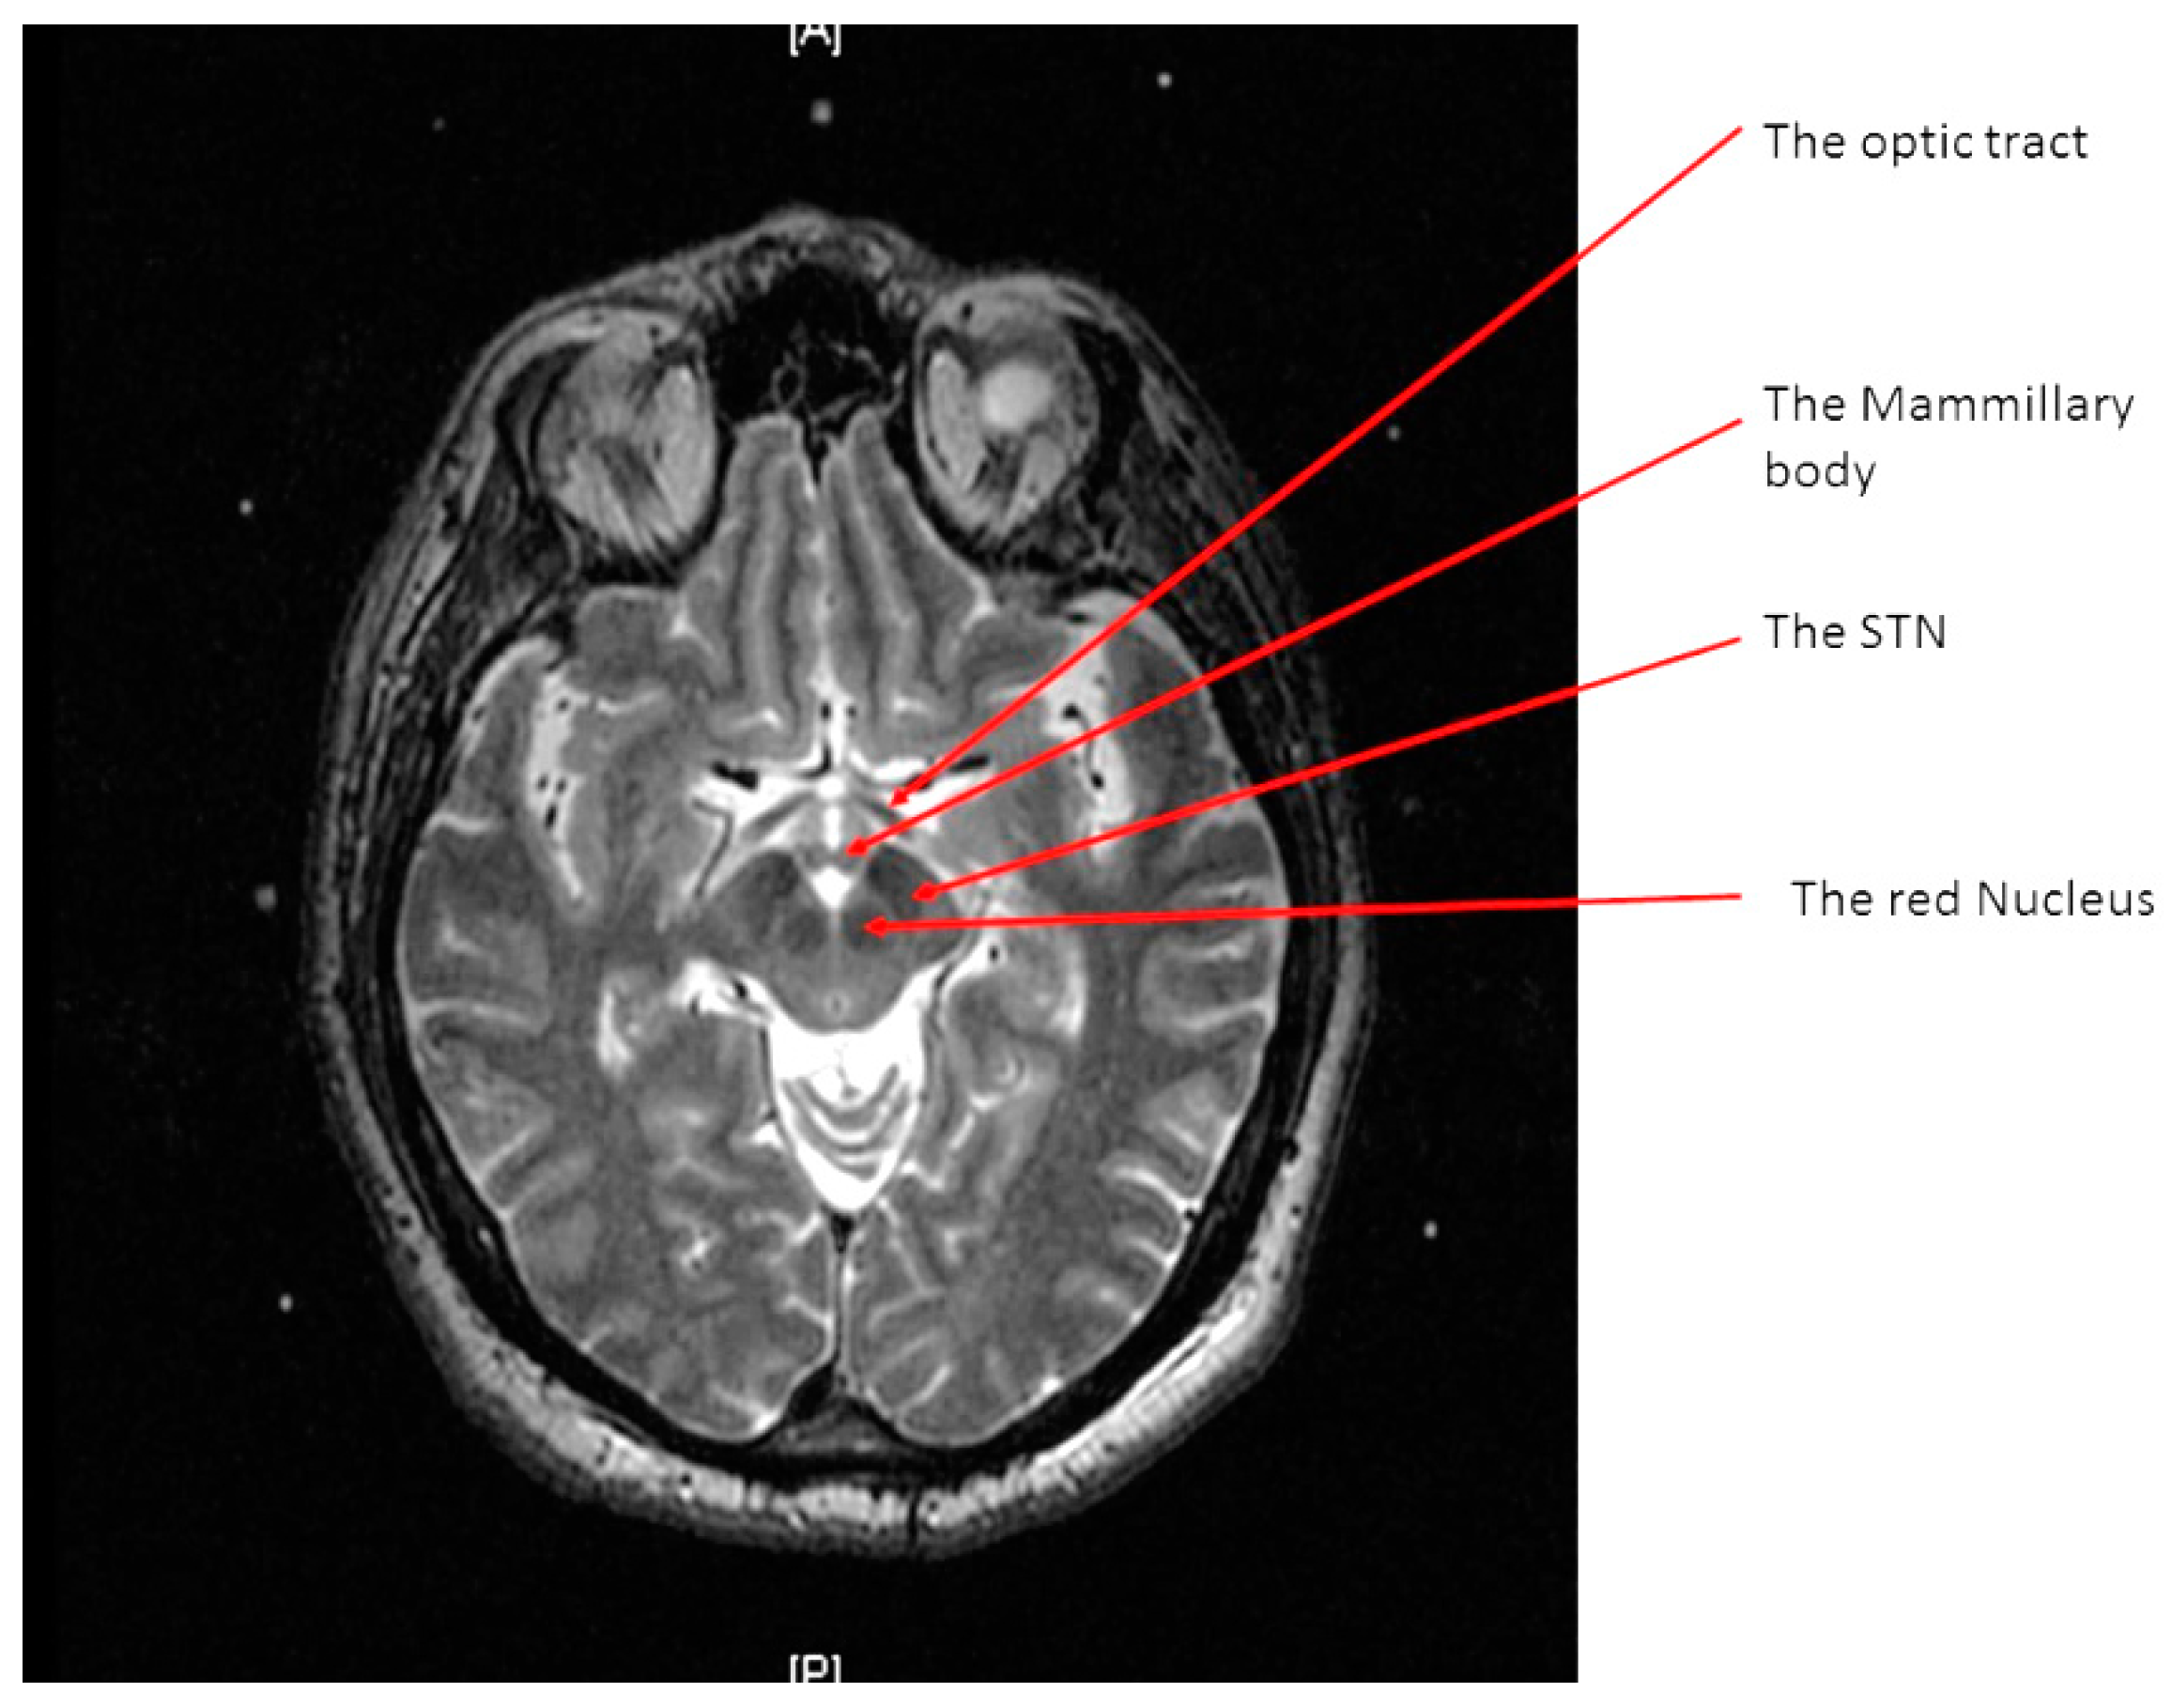

A high-resolution MRI of the patient’s brain with a 3 Tesla scanner (Signa 3T94 VHi; General Electric Medical Systems, Milwaukee, WI, USA) was done. Two main sequences were obtained. The first is a 3D T1-weighted, spoiled gradient echo imaging of the entire head (section thickness: 2 mm; field of view: 26 × 26 cm; TR: 7.0–8.0 milliseconds; TE: ~400 milliseconds; flip angle: 12; band width: 31.25 KHz; acquisition time: <7 min). The second is high-resolution, contiguous, T2-weighted, fast spin-echo imaging through the region of the midbrain and basal ganglia (section thickness: 1.5 mm; slice interval: 0 mm; matrix size: 512 × 512; field of view: 26 × 26 cm; TR: 4600–6200 milliseconds; TE: 95–108 milliseconds; acquisition time: <5 min) (Figure 1).

Figure 1.

An axial T2 weighted magnetic resonance image (MRI) at the level of the midbrain showing the two subthalamic nuclei (STN).

The STN is the hypointense structure located lateral and anterior to the red nucleus on axial T2 MRI (Figure 4) [8]. The center of the STN hypointensity was identified at the extension of a straight line drawn at the anterior margin of the RN bisecting the STN. Then, the coordinates were calculated using the same Excel worksheet.

Figure 4.